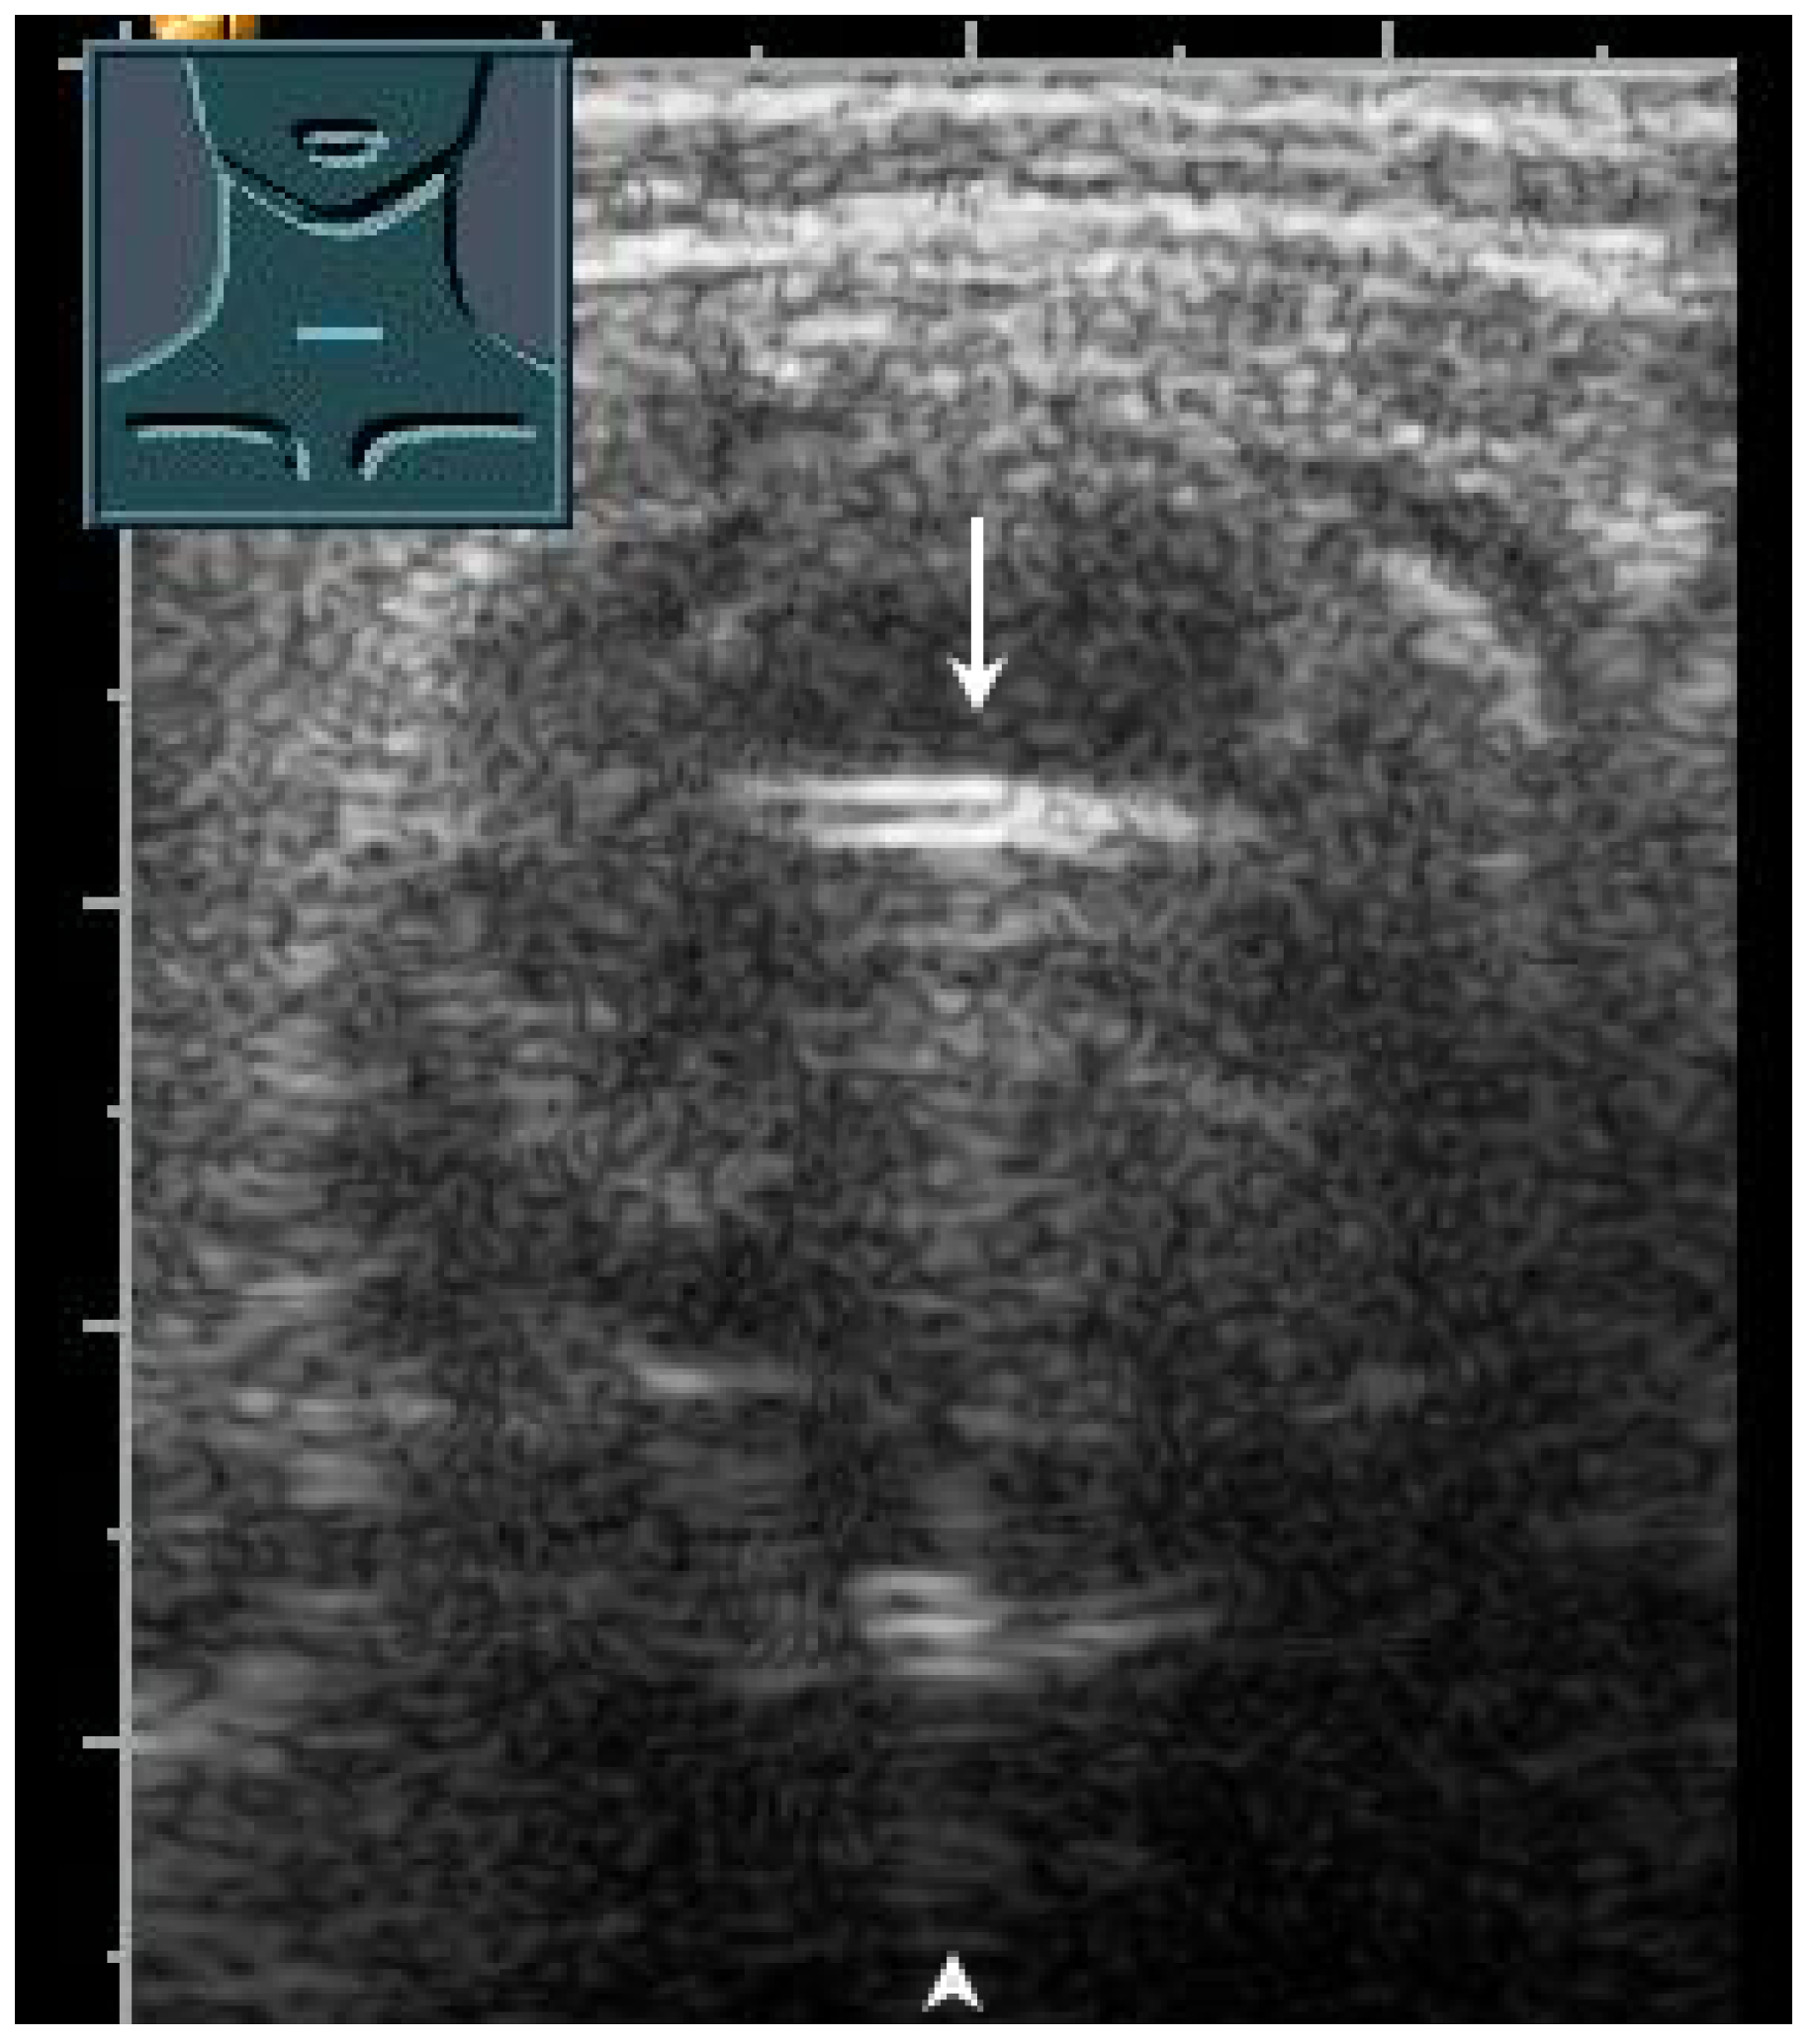

2.7. Trachea

US has proven to be a helpful method for the rapid evaluation of the trachea in the operating room, intensive care unit, and emergency department [43]. Various clinical applications include performing a percutaneous dilatation tracheostomy, detecting subglottic stenosis, predicting difficult intubation and stridor after extubation, determining pediatric endotracheal tube size, and verifying endotracheal tube location [43]. In a prospective study, to confirm the localization of the endotracheal tube after emergency intubation, US showed a diagnostic accuracy of 98.2% and can therefore be considered to be a reliable method [44]. These data were recently confirmed in a meta-analysis [45]. In correct tracheal intubation, only one hyperechoic air–mucosa interface with comet-tail artifacts and dorsal sound extinction is visualized (Figure 28). Esophageal intubation shows two hyperechoic air–mucosa interfaces with comet-tail artifacts and dorsal sound extinctions [44].

Figure 28.

Demonstration of correct tracheal intubation. Only one air–mucosa interface within the lumen of the trachea (arrow) with comet-tail artifacts (arrowhead) and dorsal sound extinction is visualized.